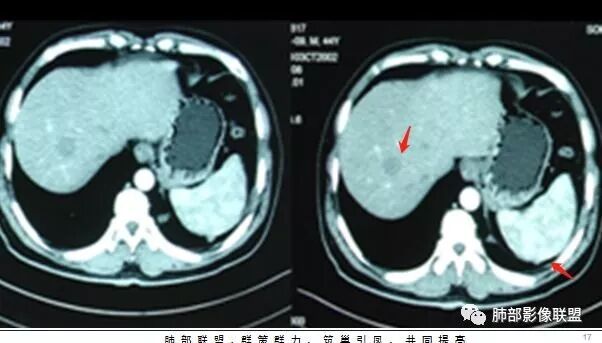

腹增强CT

南边:胸膜下,类圆形,边界清,内有坏死,典型的反晕征,支气管壁增厚不明显,支持血道来源脓毒栓子所致梗死、感染

血道来源没问题

左下叶大片类似病灶

脾大,肝内结节中央似有点状血管通过,炎性可能

2.本例应当属另一经典感染途径,肝脏感染,双肺脓毒性肺炎。大家都注意到患者的基础疾病,糖尿病。

4.本例肝脏的病灶并未出现典型肝脓肿图像特征,病灶密度及中央血管样结构显然不符合一般的囊肿。应当说,它是感染灶,但并未液化形成脓腔。